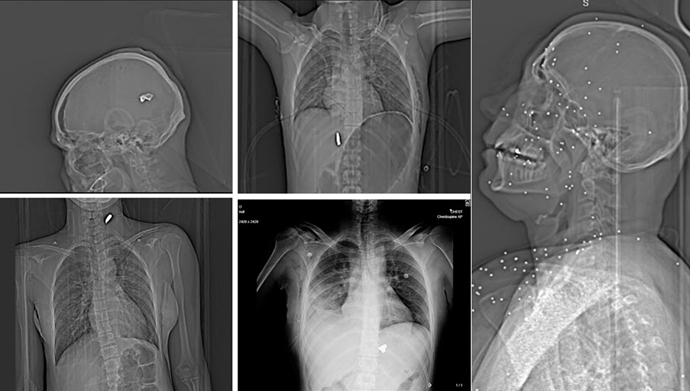

بر اساس این گزارش، بیش از ۷۵مجموعه تصویر پزشکی که همگی در جریان یک شب سرکوب خونین در ماه (دی) ژانویه ثبت شدهاند، وجود ترومای شدید ناشی از شلیک ساچمههای فلزی و گلولههای کالیبر بالا را تأیید میکند. این جراحات بهدست نیروهای سپاه پاسداران علیه معترضان و حتی رهگذران وارد شده است.

گاردین مینویسد این تصاویر شواهد تازهای از تغییری خطرناک در شیوه سرکوب اعتراضات در ایران ارائه میدهد؛ جایی که نیروهای امنیتی به جای روشهای موسوم به «کنترل جمعیت»، از مهمات جنگی و سلاحهای تهاجمی کالیبر بالا استفاده کردهاند. سوابق پزشکی بررسیشده، الگویی تکرارشونده از شلیک مستقیم به صورت، قفسه سینه و اندامهای... را نشان میدهد؛ الگویی که پیشتر در جریان اعتراضات ۱۴۰۱ - (۲۰۲۲) نیز مشاهده شده بود.

این تصاویر در قالب یک تحقیق مشترک میان گاردین و پلتفرم حقیقتسنجی فکتنامه توسط گروهی از کارشناسان مستقل پزشکی و بالستیک خارج از ایران بررسی شده است. این گروه شامل یک پزشک اورژانس، یک رادیولوژیست و یک متخصص تصویربرداری تروما بوده است. همچنین یک پزشک مستقل ایرانی تأیید کرده که نرمافزار ثبت تصاویر با سیستمهای بیمارستانی مطابقت دارد و نشانهای از دستکاری در آنها دیده نمیشود.